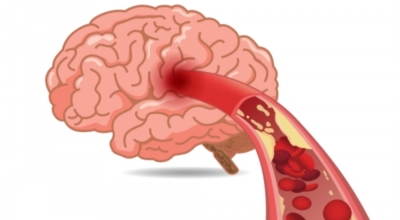

뇌경색의 가장 흔한 원인은 고혈압, 당뇨, 고지혈증 등으로 인해 뇌에 혈액을 공급하는 혈관에 뇌혈류가 차단되는 경우와 그 밖에심장 부정맥, 심근경색의 후유증 등으로 인해서 심장에 혈액이 응고된 상태가 되고 이 혈전이 혈류를 따라 이동하다가 뇌혈관을 막아 뇌졸중이 나타나는 경우도 있어요.